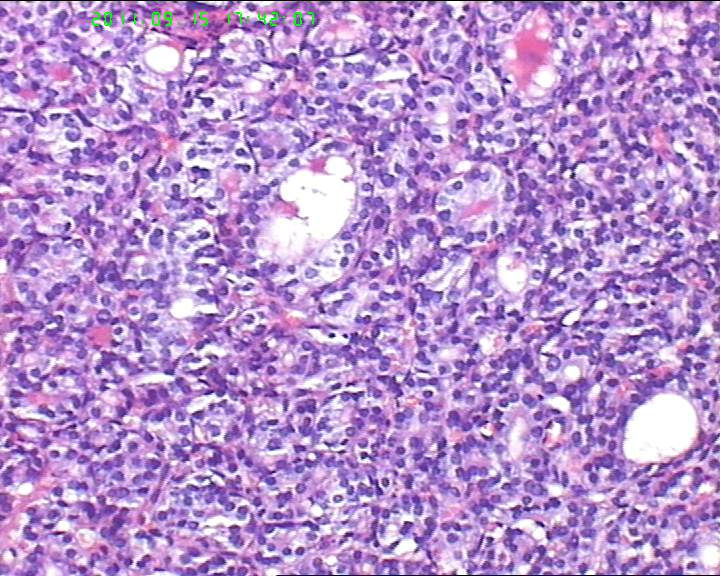

甲状腺右下极一肿物,3*3大小,切面灰红实性质韧,可见部分包膜,一侧可见一空腔,未见内容物。

38岁女性甲状腺,腺瘤?滤泡癌?图3

名称:图3

描述:20110915-3.jpg.jpg

够不够滤泡癌,要找有没有浸润。网友们,这么多图片,有包膜浸润吗(哪几张是包膜)?图12、14又是什么?

非典型腺瘤,多取材

如找不到明确的胞膜,血管浸润和正常甲状腺组织破坏,最好诊断非典型腺瘤.

非典型腺瘤,没有看到明显的血管浸润及包膜浸润

考虑为滤泡性腺癌,再补补材